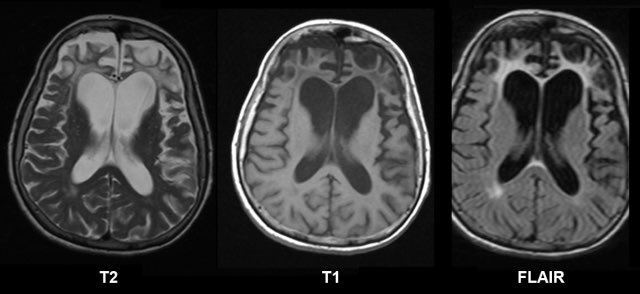

7️⃣تشخيص ضمور المخ

عادةً مايتضمن التشخيص اختباراً بدنياً يتبعه اختباراتٍ معينةٍ،ويظهر ضمور الدماغ في عمليات مسح تصوير الدماغ منها:

*الرنين المغناطيسي(MRI)الذي يخلق صوراً دماغيةً عالية الدقة للتشخيص